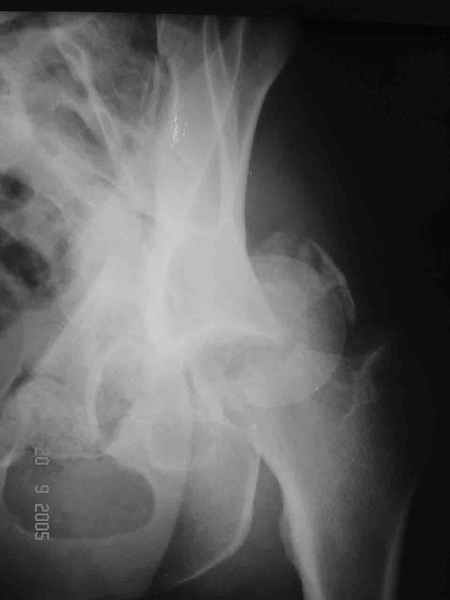

При поступлении в госпиталь 3.06.03

Больной 18 мая 2003 года в автоаварии получил перелом левой вертлужной впадины, вывих бедра. Госпитализирован в один из стационаров области.Вывих вправлен. В последствии бедро вывихивалось еще дважды. На консультацию был представлен снимок от 19.05.03г., больной переведен к нам 3.06.03г. Снимок при поступлении - перелом впадины, задне-верхний вывих бедра. 05.06.2003 г. выполнено открытое вправление вывиха левого бедра и остеосинтез стенки вертлужной впадины двумя винтами. Послеоперационный период без осложнений. Объем движений в левом тазобедренном суставе восстановился полностью. Выписан на амбулаторное лечение в удовлетворительном состоянии с рекомендациями 3 месяца ходить на костылях без нагрузки на оперированную конечность. На контрольных рентгенограммах левого тазобедренного сустава 13.10.2003 г. - признаки консолидации перелома; плотность, форма головки и состояние суставных поверхностей удовлетворительные. Разрешена дозированная осевая нагрузка, на конечность с использованием дополнительной опоры. 19.12.2003 г. больной обратился с жалобами на боли в левом тазобедренном суставе. На рентгенограммах левого тазобедренного сустава 19.12.2003 г., 20.02.04г. - асептичекий некроз головки бедра. 5.04.04г. - эндопротез. Сейчас ходит без трости, не хромает. Особенность эндопротезирования - при удалении винтов прослежена линия перелома заднего края впадины и предложено установить чашку несколько меньшего диаметра, чтобы она была покрыта несломанной частью.